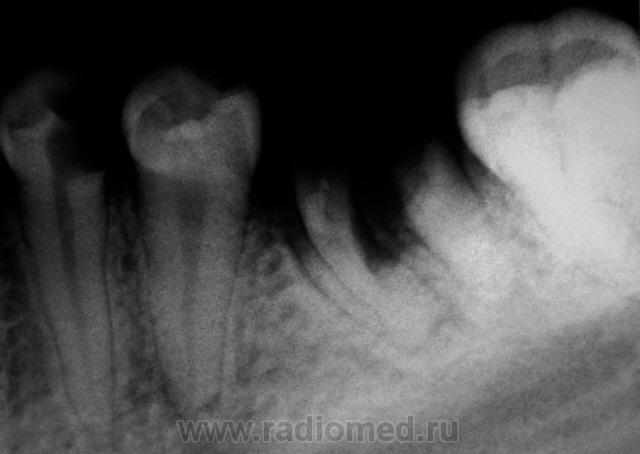

Это уже просто кариозные монстры какие-то!

... и гранулематозные...

Сегодняшний "улов"